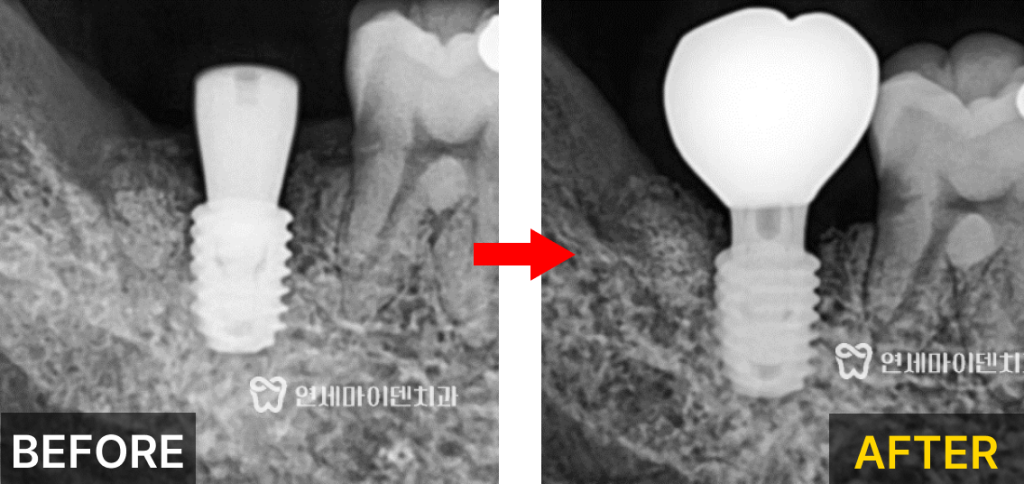

타원에서 받으신 겁니다.실제 엑스레이 상으로도

치아 뿌리 주변의 치조골이 까맣게 소실돼 있었고,신경관이 바로 인접해 보이는 모습이 관찰되었습니다.

임플란트 식립이 가능한 상태임을 확인할 수 있었습니다.따라서 발치 즉시 임플란트 식립을 진행하기로 하였습니다.

사전에 모의 수술을 통해 식립 위치를 설계하였습니다.이후 발치 즉시 임플란트를 시행하였고,

치아 발치 후 내부에 남아있는 염증 조직을 철저히 제거하였습니다.치조골이 부족한 부위에는 뼈 이식술을 병행하여

임플란트의 고정력을 확보하였습니다.

수술 2주 후 잇몸이 잘 아물고 있는 것을 확인했고,

3개월이 지난 시점에서 2차 수술과 함께

최종 보철물 제작을 진행하였습니다.발치 즉시 임플란트는 우리 신체의 치유 잠재력을

최대한 살릴 수 있는 방법이기 때문에발치 후 3개월만에 잇몸 뼈가 차오르고

임플란트 후 보철물까지 완성할 수 있었습니다.임플란트 성공률을 높이기 위해 확인해야 할 것